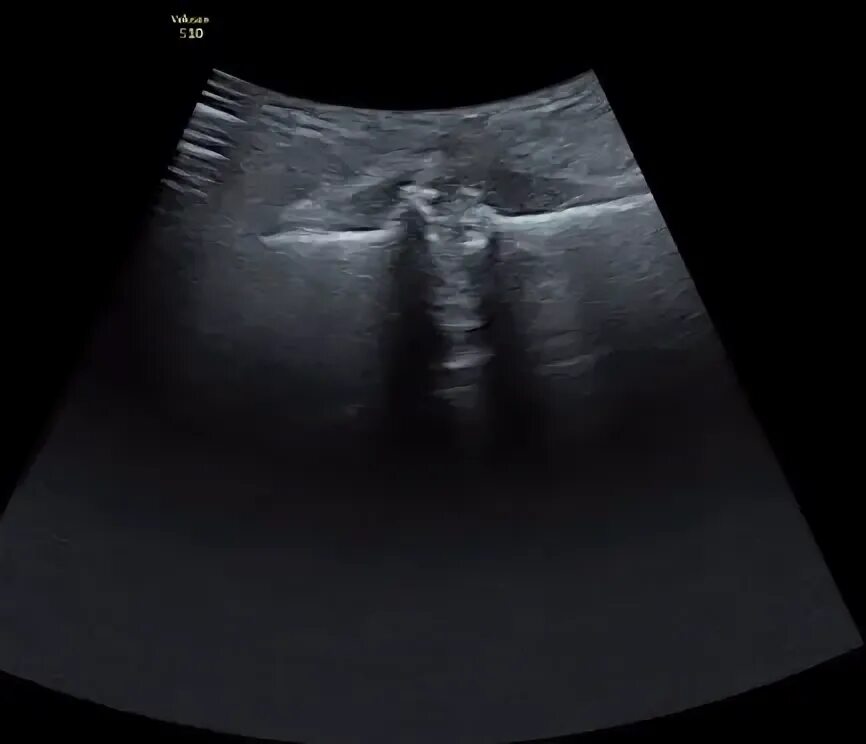

При симфизите делают кесарево